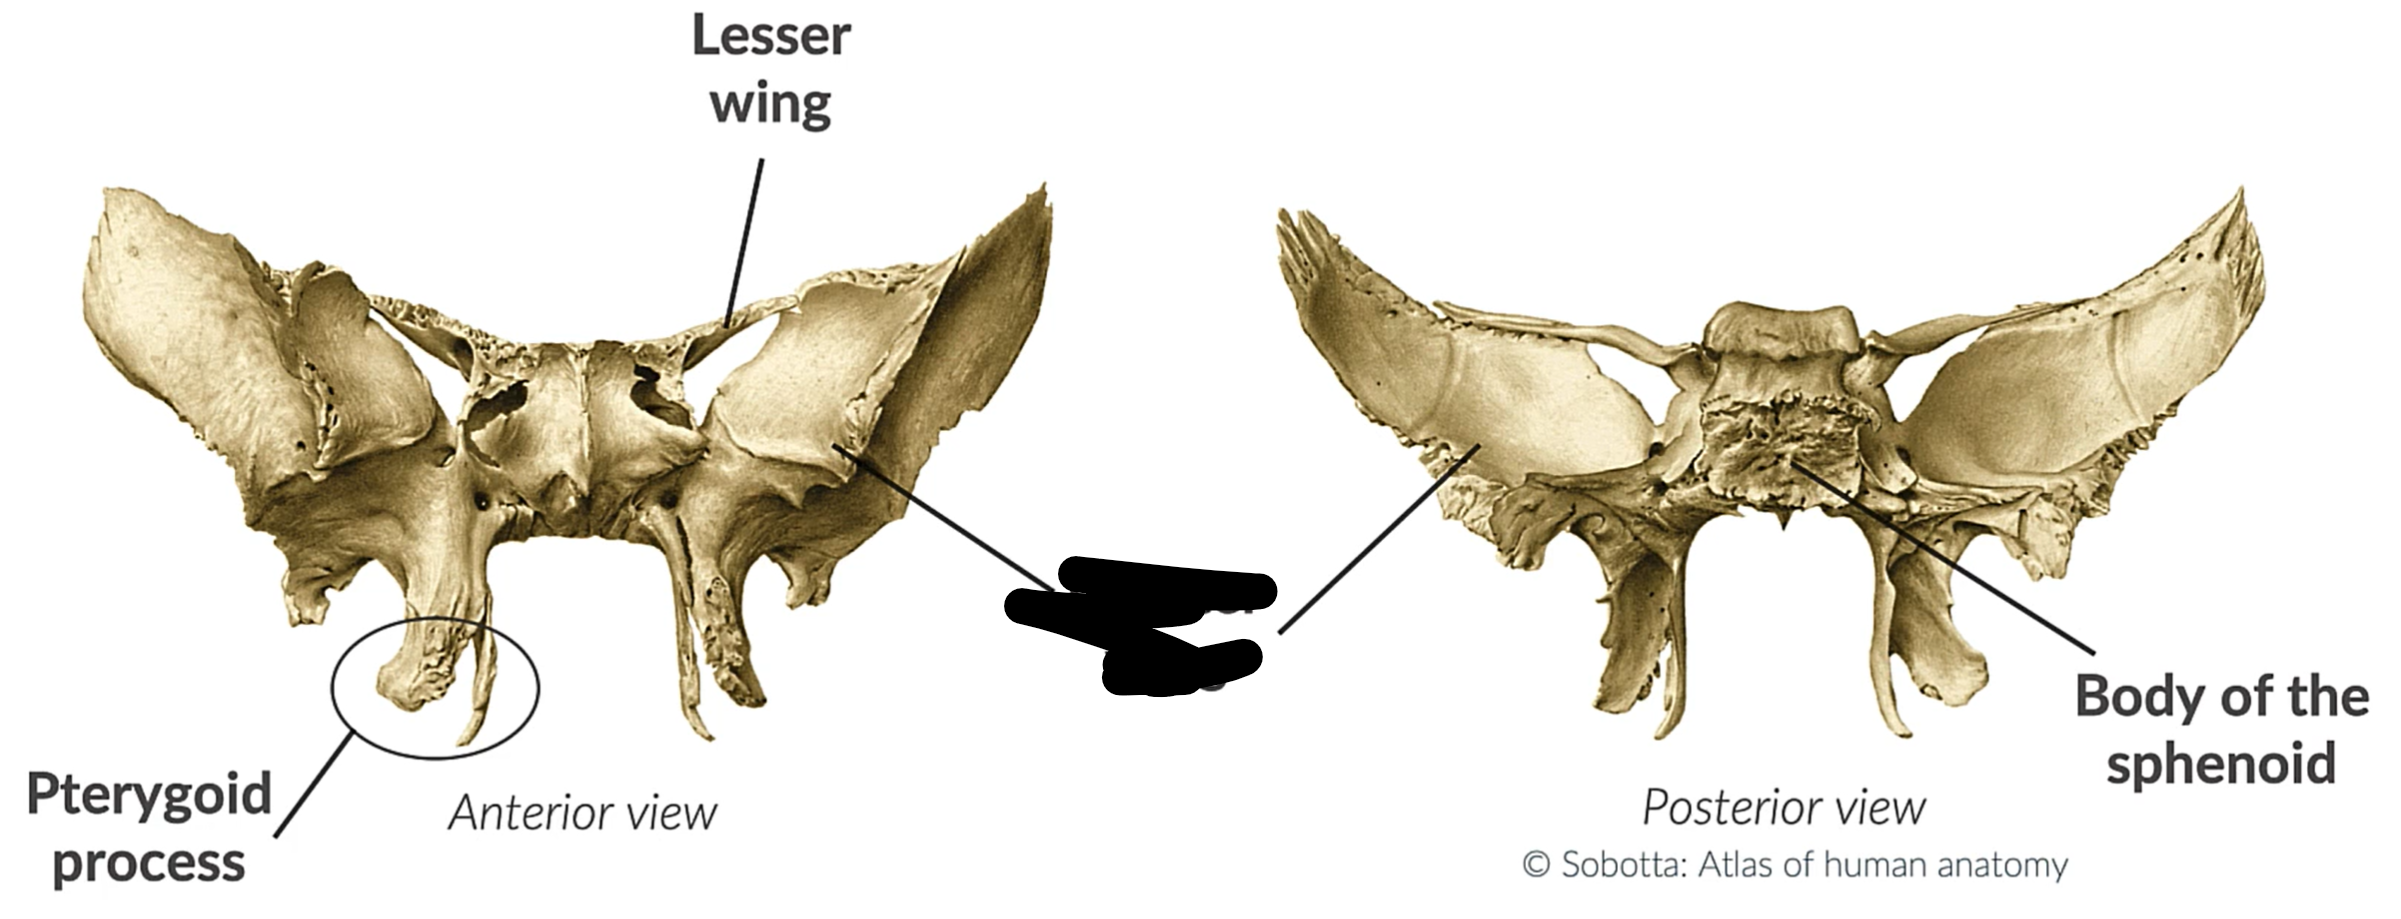

What bone is this?

Sphenoid bone

Lesser wing

Greater wing

Pterygoid process

Body sphenoid bone